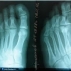

Болезнь Келлера- дистрофические изменения и омертвение костной ткани, проявляющиеся как следствие местных расстройств кровообращения, возникающих в результате врождённых, обменных, травматических и других воздействий.